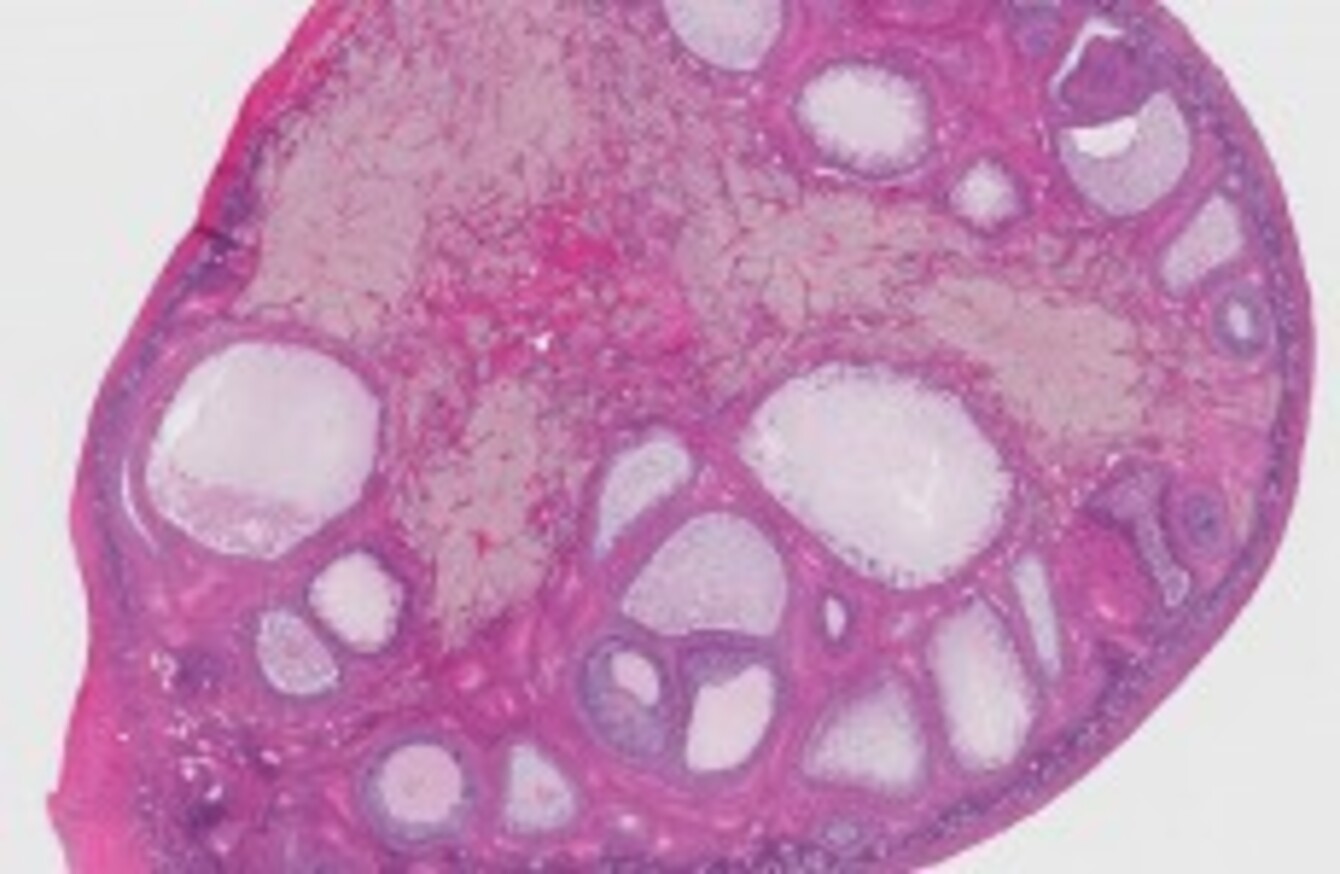

Ovarian cancer is cancer of the ovaries that produce eggs. Both ovarian cancer and ovarian cysts typically do not produce symptoms until they are very large or when the cancer has advanced. Most women with these symptoms do. If they do occur, some ovarian cancer symptoms may include: When this occurs, they may share similar signs and symptoms, for example: At the same time, studies have found that complicated surgeries (cytoreduction surgery for ovarian cancer) have a better prognosis if performed by specialists in ovarian cancer (by gynecologic oncologists) in a center which performs a significant volume of these surgeries, rather than by general gynecologists who do fewer of these surgeries. The most common symptoms include: If you have had a breast and/or ovary removed, talk to your doctor to learn more about your personal cancer risk. It is for these reasons ca125 is not recommended as a screening test for women with no symptoms. Trouble eating or feeling full quickly. Cancer kills thousands of people yearly and only a few live to say they beat it. Signs and symptoms of ovarian cancer may include abnormal vaginal bleeding or discharge, abdominal pain, reduced appetite, bloating, pelvic pain, constipation and an increased urge to urinate. Ovarian cancer symptoms can be unclear and difficult to detect before the cancer spreads.